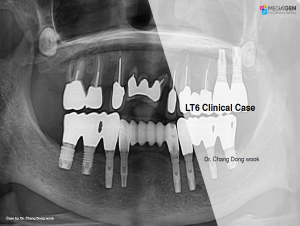

LT6 Clinical Case

Dr. Chang Dong Wook,Bone regeneration,Mandibular Anterior,GBR,LT6,Clinical case

English

2019-10-01

PDF

4.49 Mb

Clinical cases

184